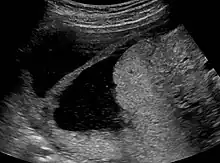

Ultrasound view.

Amniotic sheet on ultrasound